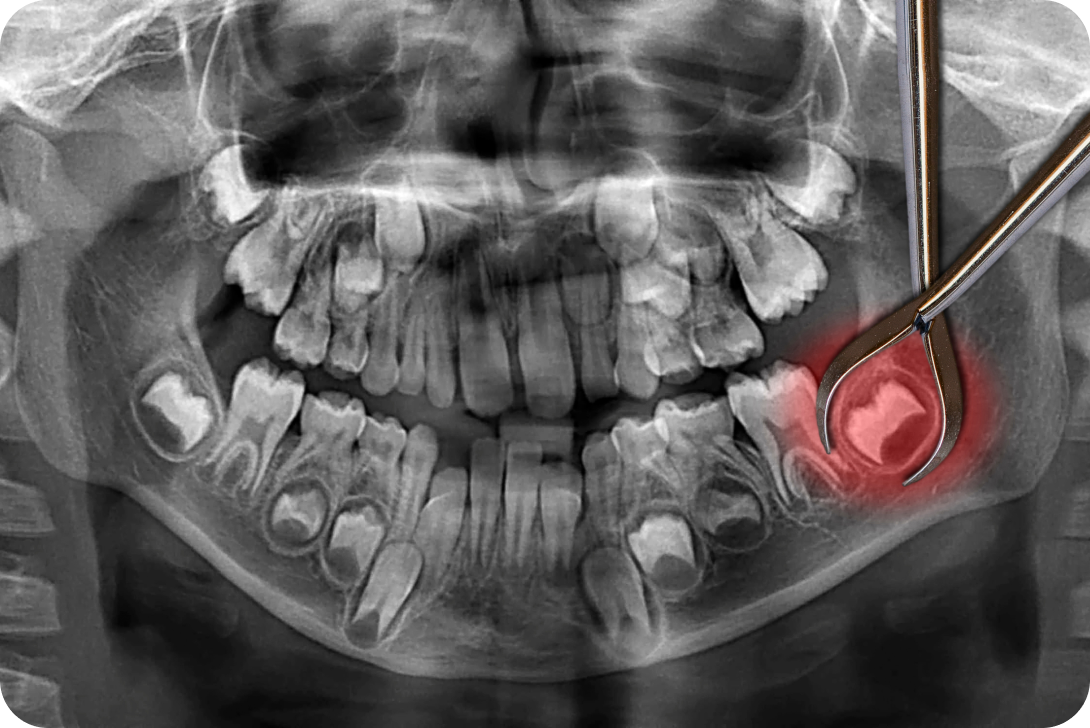

L’implantologie permet de replacer une dent en cas de maladies dégénératives, d’infections, de traumatismes ou autres. Un dispositif, appelé l’implant, permet de remplacer la racine de la dent manquante. Une couronne sera alors placée sur cet implant pour remplacer la partie extérieure de la dent. Notre dentiste à Toulouse peut traiter les cas avancés nécessitant une ou plusieurs extractions bucco-dentaires et vous permettre de retrouver l’intégrité de votre denture après une carie ou un choc.